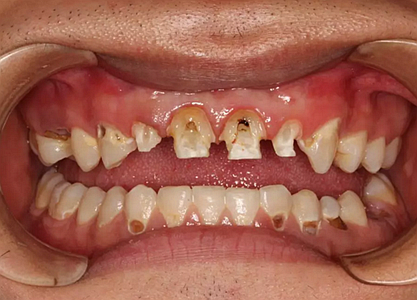

現(xiàn)在剩下的任務(wù)就是為我其他的兄弟姐妹們治療了。需要做根管的做根管,需要做冠的做冠,需要樹脂充填的做樹脂充填。前前后后主人帶我們進行了12次的復(fù)診,歷時6個月,現(xiàn)在的我們是這樣的

再來看看曾經(jīng)的我們

經(jīng)歷了如此長久的治療,主人應(yīng)該也是吸取了教訓(xùn),或許以后會改了不良的生活習(xí)慣,而我們經(jīng)歷了這段涅槃之旅,雖然也煥然一新,重塑了容顏,卻也是歷經(jīng)辛苦,如果主人能好好待我們,其實這樣的痛苦本不需要經(jīng)歷。